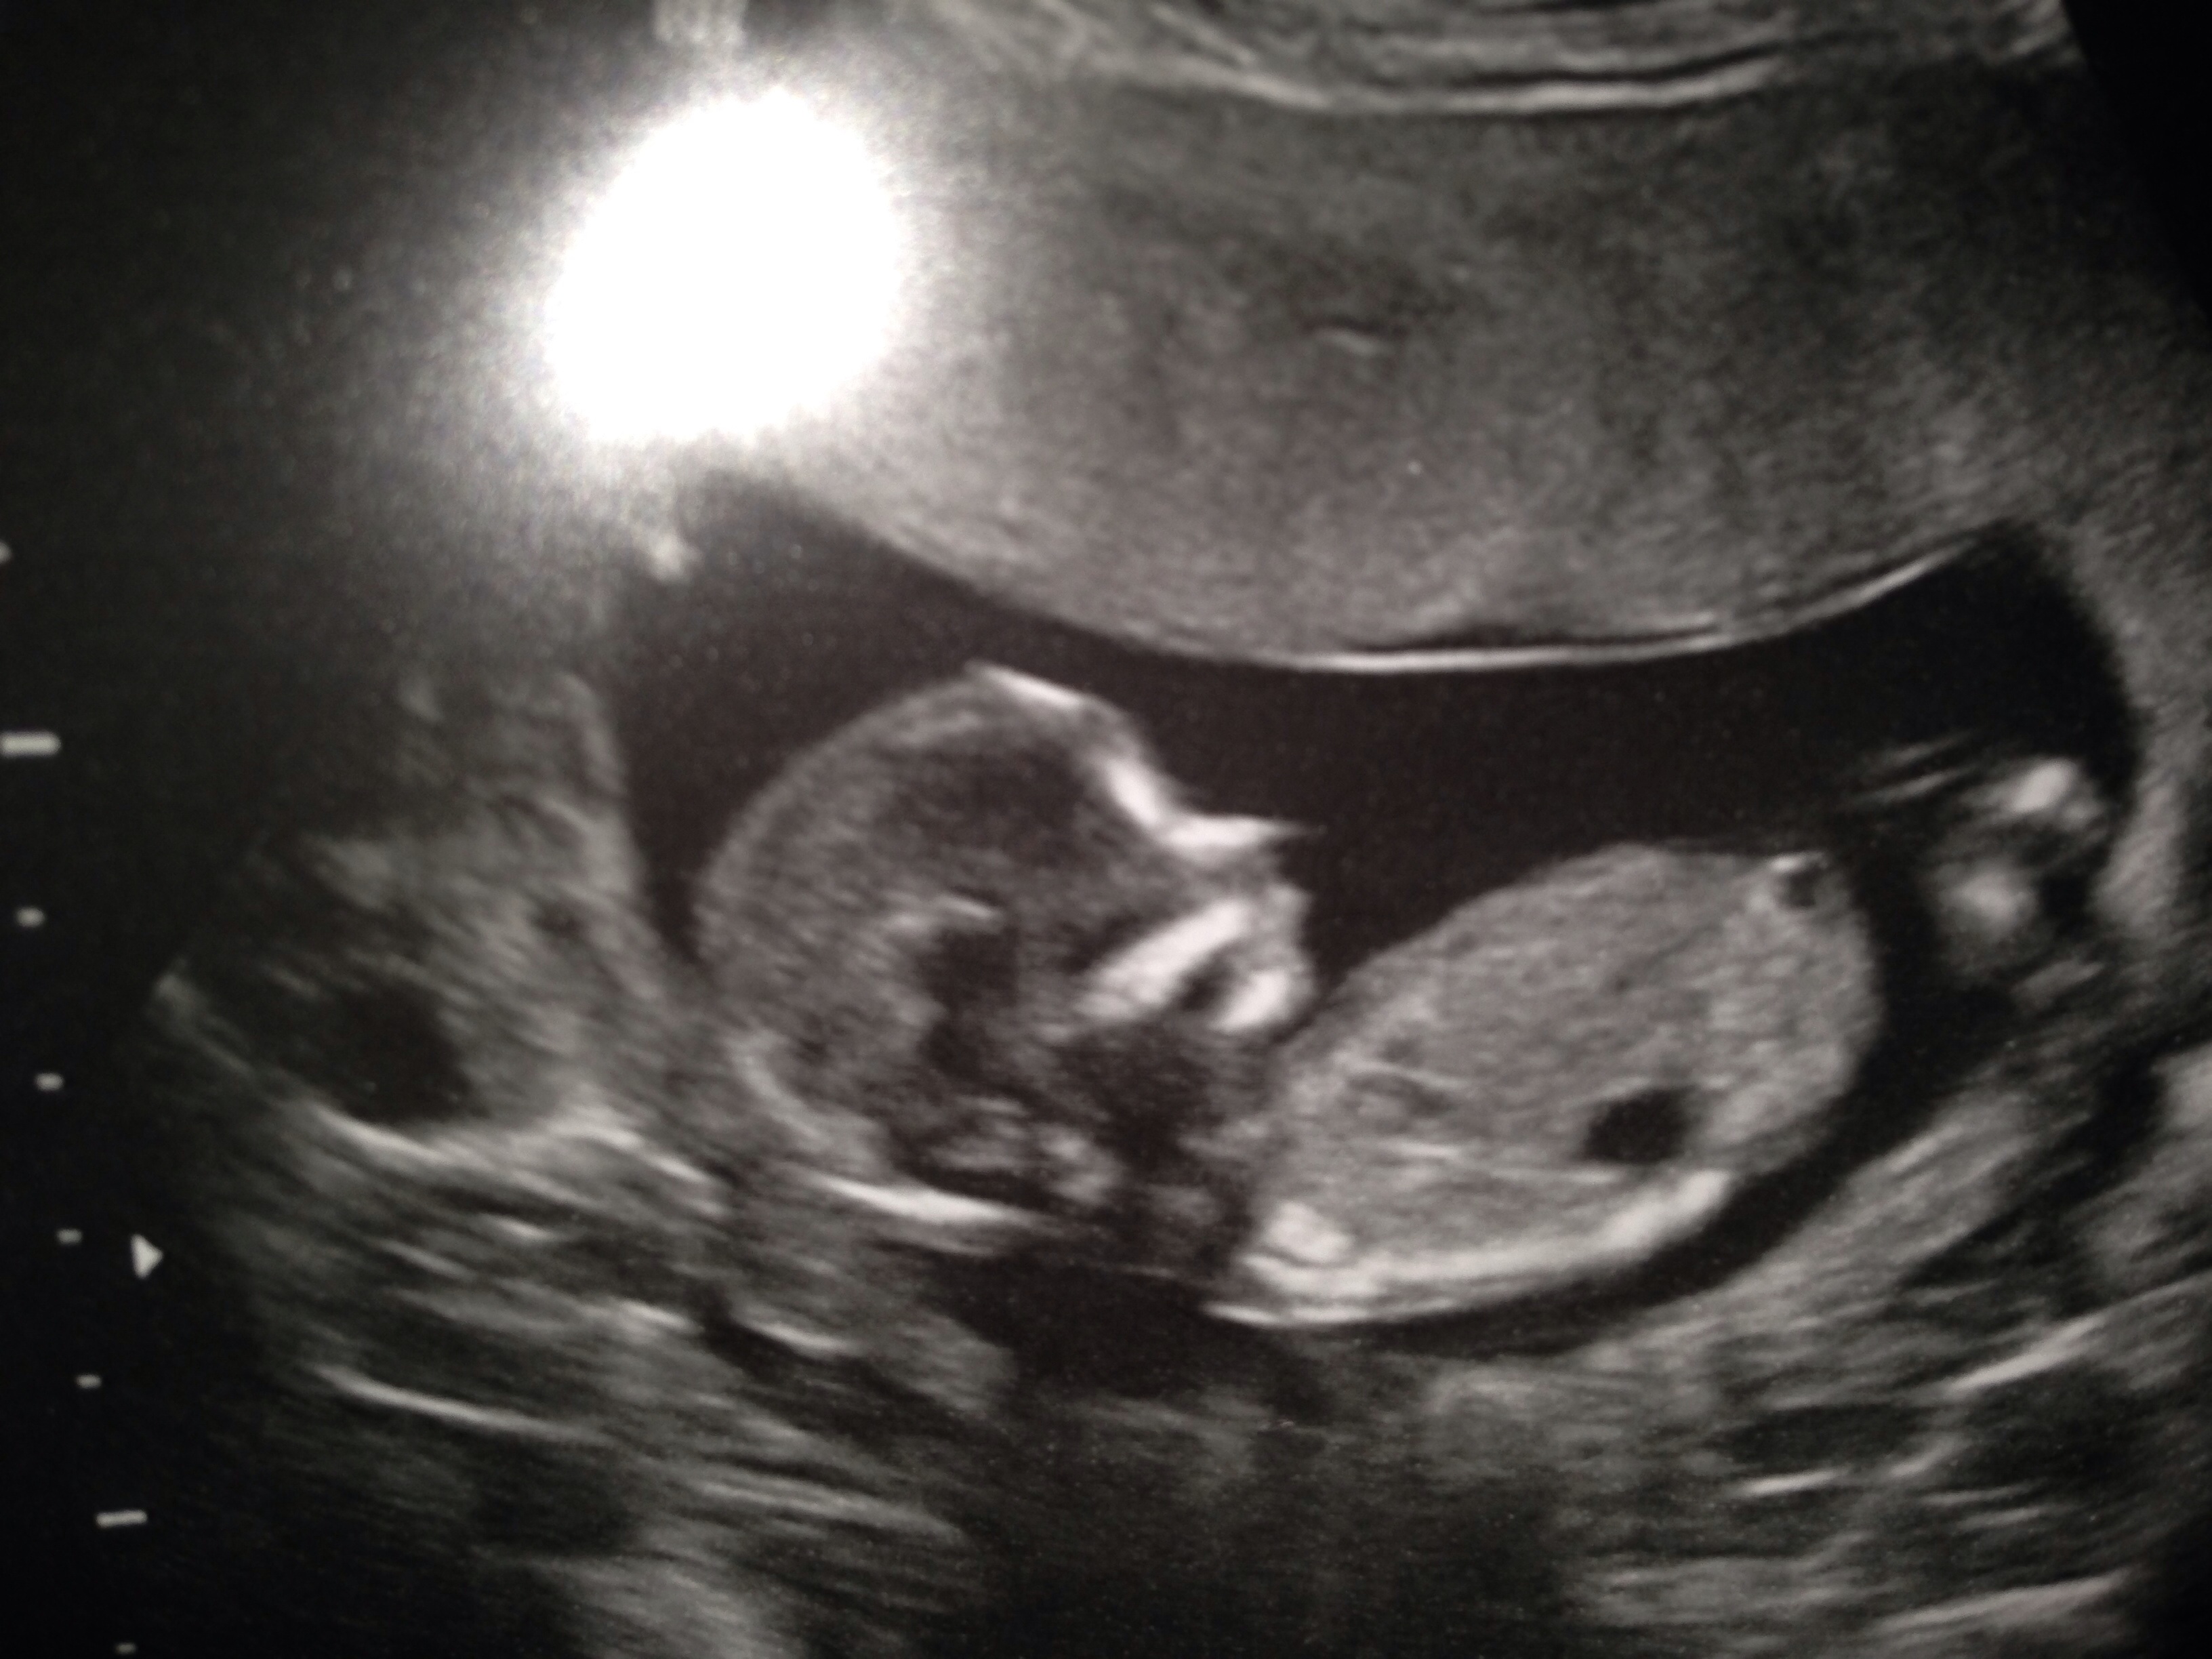

Hello! Just had my first scan of a completely surprise 4th pregnancy and found out I am 14 weeks!DH is desperate to know the gender as we already have 4 boys and I'm assuming that's all we make! I had never heard of the nub theory until today and have no idea if my picture even shows one. I'd be so grateful if anyone could help point out what I'm looking for or even have a guess for us! Thank you :-) xxxAttachment 18899

Attachment 18898